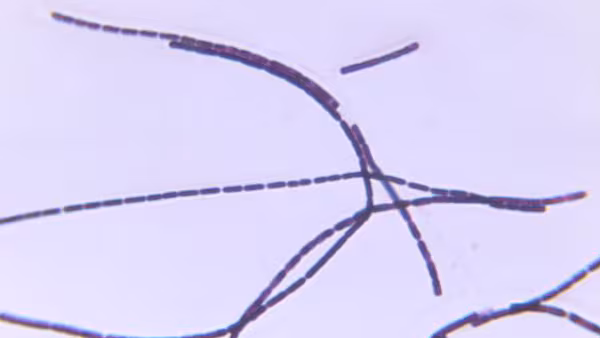

The New Hampshire Department of Health and Human Services performed an initial qualitative environmental sampling at the event site for the presence of Bacillus anthracis spores, a bacterium that causes anthrax.

Three samples from the event site grew B. anthracis, and the isolates were sent to CDC for genotyping.